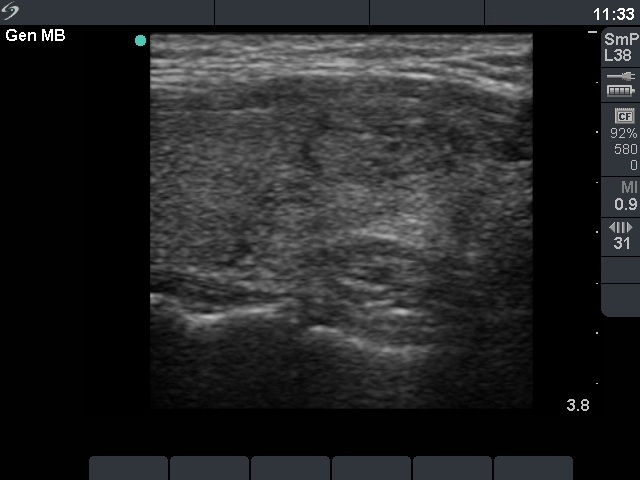

Benign nodular hyperplasia - Case 38. |

Clinical presentation: a 39-year-old woman was referred for an evaluation of weight loss.

Palpation: a nodule in the lower part of the left lobe.

Functional state: euthyroidism with TSH-level 1.17 mIU/L, FT4 19.0 pM/L.

Ultrasonography: there was a small hypoechogenic lesion in the right and a moderately hypoechogenic nodule with microcalcifications in the left lobe. The vascularization was not specific.

Cytological diagnosis: benign, colloid goiter.